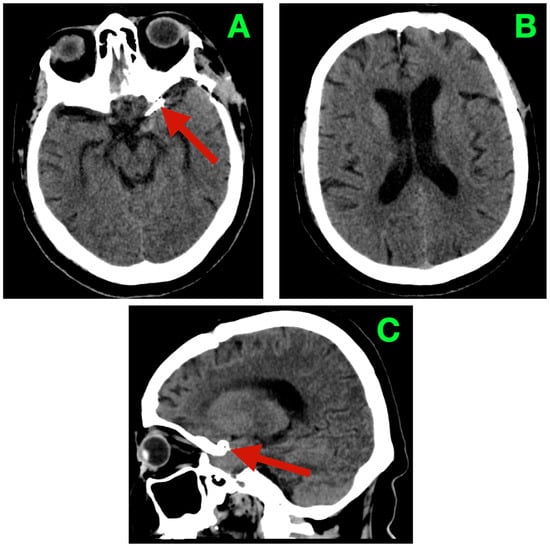

2.5. Imaging Findings and Morphometric Analysis